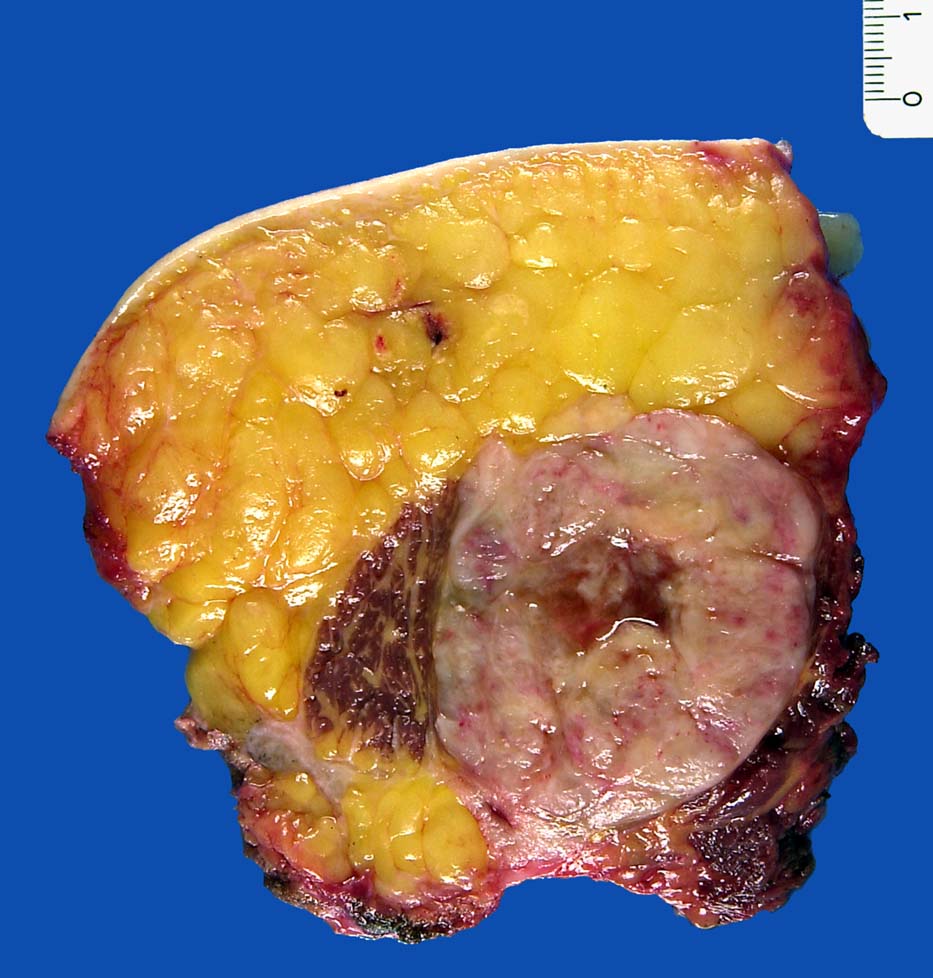

Pleomorphes Liposarkom

Haut- und Weichteilexzisat mit randständigen Skelettmuskulaturanteilen (Gluteus maximus). Auf Schnitt erkennt man einen direkt innerhalb des Musculus gluteus maximus gelegenen 9.5cm im Durchmesser messenden weisslichen, fasrigen, zentral nekrotischen Tumor.

Pleomorphes Liposkarkom

Pleomorphes Liposarkom-Rezidiv; St. n. Radiotherapie.